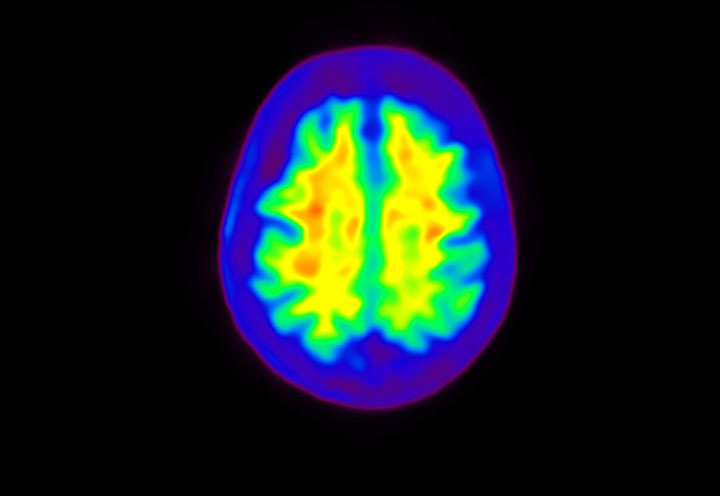

Head / Case4 : Amyloid

Courtesy : Kindai University Hospital

- Imaging protocol

- Injected dose: 3.21 MBq/kg, 18F-Flutemetamol

- Uptake time: 100 minutes

- Scan time: 20 minutes